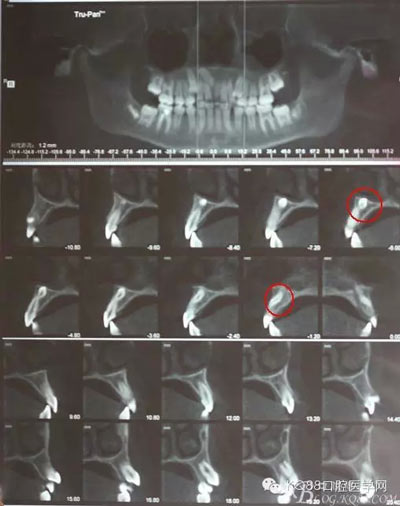

圖3.倒置多生牙位置高,又接近鼻腔,為了減小創(chuàng)傷,加拍CBCT檢查:倒置多生牙牙冠已經(jīng)突破鼻底骨質(zhì),拔除后有可能出現(xiàn)鼻腔出血,術前已經(jīng)告知患者手術風險。多生牙牙根偏向唇側,為了減小創(chuàng)傷,決定從唇側做切口入路。